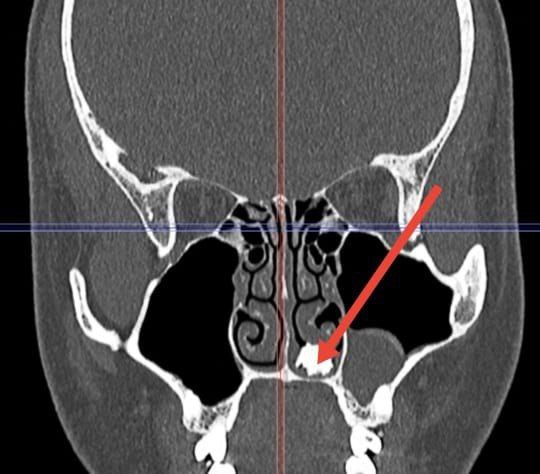

Врачи Долгопрудненской больницы достали из носа 22-летнего молодого человека молочный зуб. Он обратился с жалобами на продолжительный насморк. Проведенная диагностика выявила, что в полости носа пациента присутствует образование костной плотности.

— Во время операции, которую выполнили отоларингологи стационара Наиля Вихарева и Елизавета Ершова, был извлечен неизвестно как попавший и неизвестно, сколько пролежавший в носовой полости, покрытый грибковым содержимым молочный зуб, — сказал заместитель главного врача Долгопрудненской больницы по хирургии Евгений Кутырев.